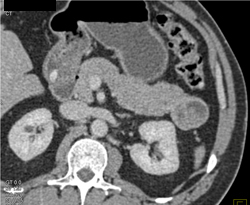

Diagnosis

Intraductal Papillary Mucinous Neoplasm (IPMN)